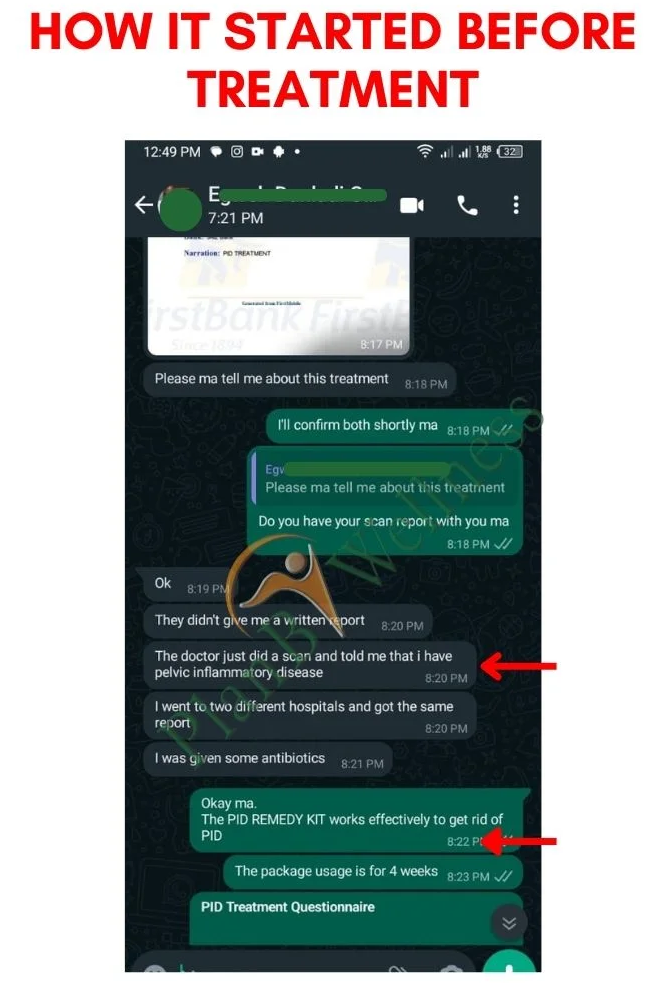

Our Happy Customers Who Love The PID Remedy Kit

Real Reviews From Real People

Our Happy Customers Who Love The PID Remedy Kit

Real Reviews From Real People

Support & Follow-Up with a Dedicated Health Advisor

You’re not just buying a product; you’re gaining a partner in your healing journey.

With this bonus, you’ll be assigned a dedicated Health Advisor who will guide you step-by-step via WhatsApp or phone call.

From tracking your progress to answering your private questions, you will have expert support anytime you need it.

We will monitor your improvement to ensure the infection is gone for good.

You never have to walk this road alone again.